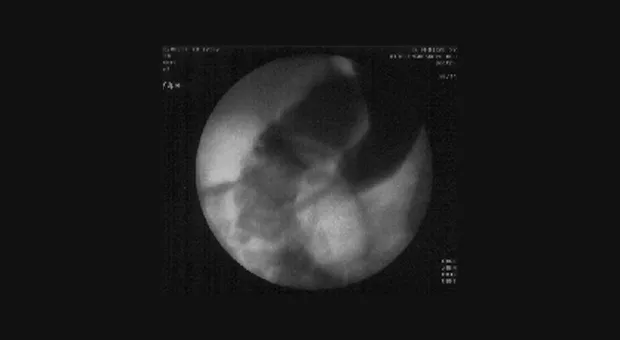

На рисунках 3-4 представлен случай неоперабельного рака поджелудочной железы с поражением нижней трети холедоха и механической желтухой. На первом снимке в область опухолевой стриктуры введен баллон-дилататор, на втором виден установленный стент.